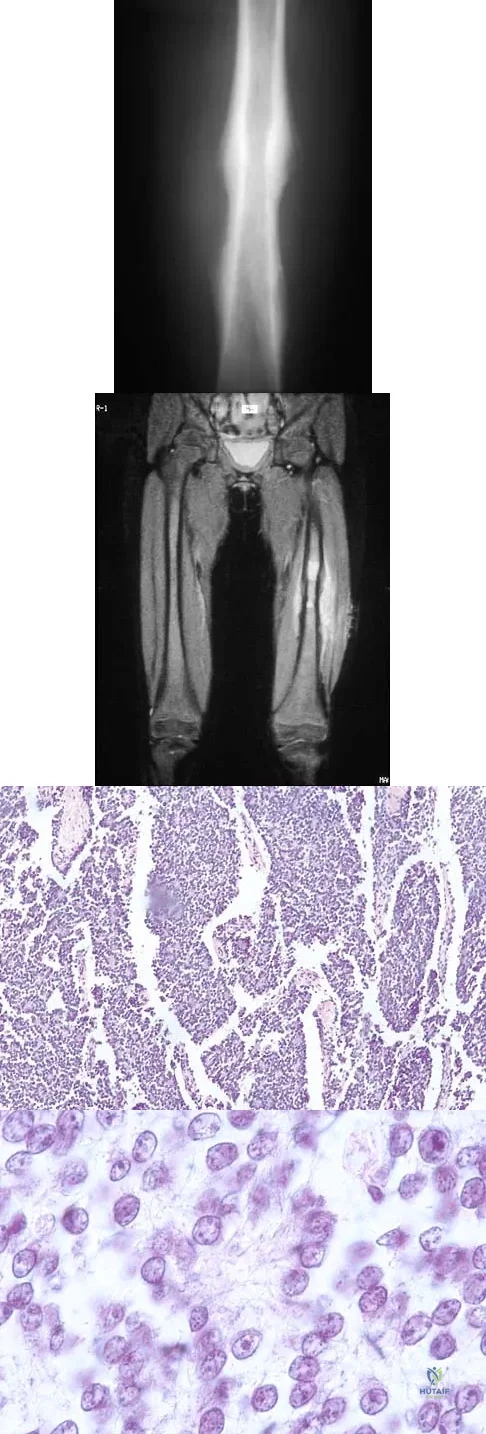

A 30-year-old man has had intermittent swelling of his right ankle for the past 6 months. He denies any history of trauma. Radiographs reveal osteolytic changes on both sides of the joint. An axial CT scan and a T2-weighted MRI scan are shown in Figures 40a and 40b. He undergoes surgical excision. An intraoperative photograph and a biopsy specimen are shown in Figures 40c and 40d. What is the most likely diagnosis?

Explanation